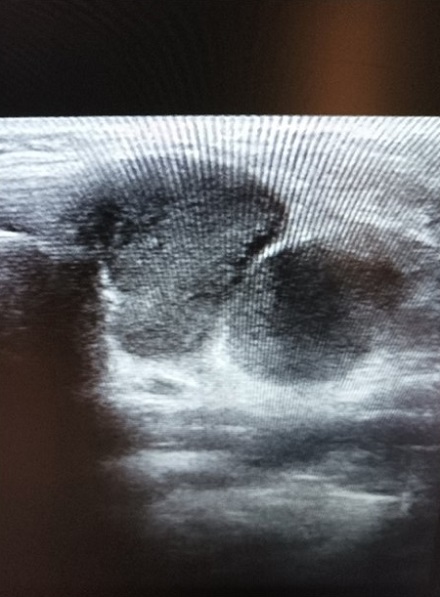

Caso 2. Niña de 14 meses que viene a la consulta por bulto cervical anterior de un mes de evolución, sin otros síntomas y muy buen estado general. Ecografía en AP: cervical anterior en la línea media formación anecoica, bien delimitada, con refuerzo posterior, que mide 1/0,7 cm, sin flujo Doppler, aspecto de quiste simple (Figura 2). Con la sospecha de quiste tirogloso se deriva a Cirugía. Actualmente está pendiente de intervención.

| Figura 2. Ecografía: cervical anterior en la línea media formación anecoica, bien delimitada, con refuerzo posterior |